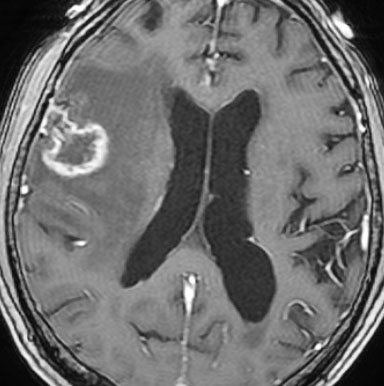

2年後 放射線壊死の進行

定位放射線治療後約2年,前の画像からはわずか3ヶ月後のMRIです。また右前頭葉の転移病巣が再発したかのように見えます。周囲の浮腫も広がって,左の片麻痺が悪化しました。しかし,ガドリニウム増強されて白くリング状に写る部分が不整形でまわりがギザギザしています。ステロイドを投与しましたが改善せずに悪化傾向を示しました。